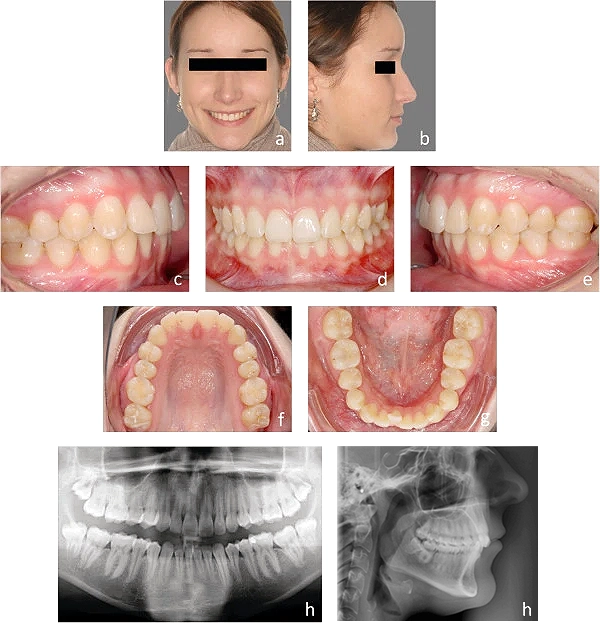

با دوربین موبایل، عکسهایی مانند تصاویر مقابل از خود تهیه و بارگذاری نمایید.

a) عکس لبخند از نمای روبرو در حالی که دندانهای عقبی روی هم هستند.

b) عکس با لبهای بسته از نیمرخ در حالی که دندانهای عقبی روی هم هستند.

c و e) عکس از نیمرخ به نحوی که دندانهای عقبی روی هم هستند و تمامی دندانها در تصویر دیده شوند.

d) عکس دندانها از نمای روبرو در حالی که دندانهای عقبی روی هم هستند و تمامی دندانها در تصویر قابل مشاهده باشند.

f و g) عکس از قوس دندانی هر فک مطابق تصویر نمونه به گونهای که از دندانهای جلویی تا آخرین دندان قابل مشاهده باشند.

h) در صورت داشتن عکس OPG و … آن را نیز بارگزاری نمایید.